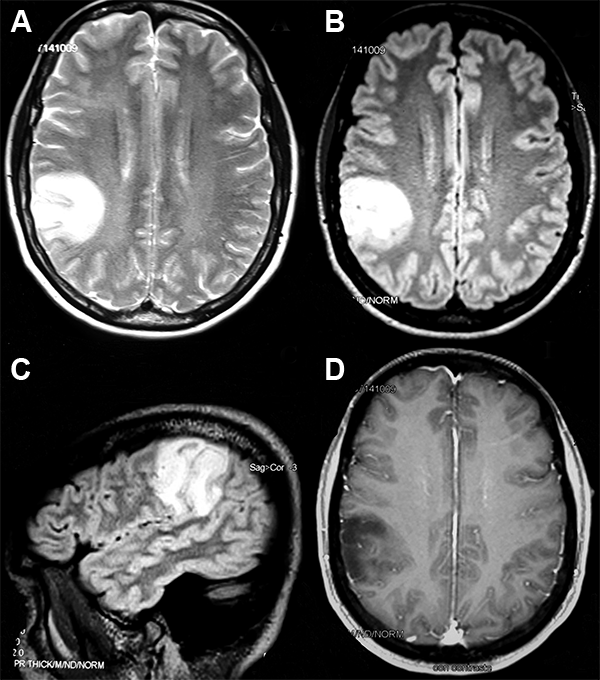

Paciente de 49 años de edad, que en noviembre de 2012 presentó crisis de inicio focal sin alteración de la consciencia de tipo autonómica. Las neuroimágenes mostraron una lesión temporoparietal derecha (fig. 1 A-D). Inició tratamiento con fármacos antiepilépticos -DFH- y por rash pasó a levetiracetam. En julio de 2013 se realizó resección parcial de la lesión (área elocuente). La anatomía patológica (AP) informó: oligodendroglioma GII, 1p19q con deleción parcial. Continuó sin tratamiento oncoespecífico y con controles por neuroimágenes. En 2018 concurrió al Instituto Roffo para continuar tratamiento. El examen neurológico fue irrelevante; continuaba con crisis focales. Se solicitó nueva neuroimagen y se ajustó dosis de levetiracetam. La revisión AP (fig. 2 A-F) informó hallazgos morfológicos clásicos de oligodendroglioma, pero con un perfil inmunohistoquímico: ausencia de codeleción 1p19q, IDH1 mutado, ATRX negativa (mutada), sobreexpresión del TP53 y un Ki67 2% (bajo), en relación a un fenotipo astrocítico; corresponde a un astrocitoma difuso IDH1 mutado. Se indicó tratamiento quimioterápico con temozolomida en ciclos de 5 días consecutivos c/28 días. La determinación de no estaba disponible al momento del caso clínico.

Figura 1: RM de cerebro (cortes axiales en secuencia T2 -A- y FLAIR -B y C-). Lesión de bordes nítidos, corticosubcortical frontoparietal perirrolándica derecha, hiperintensa, con efecto de masa local y colapso de surcos. D) Corte axial (secuencia T1c/ gadolinio). La lesión se muestra heterógénea iso/hipointensa con muy tenue realce tras la administración del contraste.